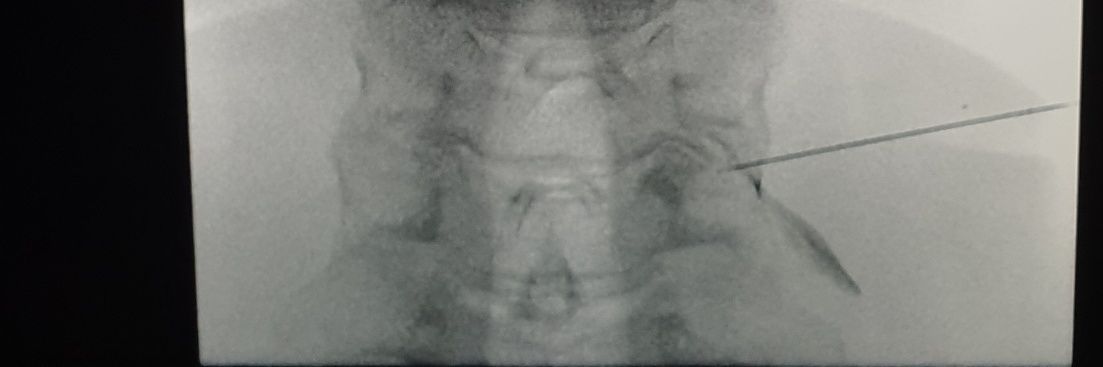

See how quickly the florid metallosis progresses. The outline of the dislocated poly can be clearly made out.

Neeraj Purohit tweet media